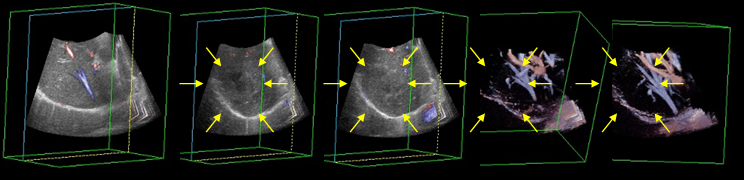

検査科ではこの度、新型超音波診断装置を導入致しました。

この機種は、浅い場所に存在する乳線などの病変には有用で、病変部位の硬さを映像化するエラストグラフィー機能を備えております。良性疾患だと柔らかく、悪性疾患だと硬い事が多い

とされており、その解析が可能となりました。 また、今までの超音波検査ではほとんど表示出来なかった乳線疾患の微細石灰化を抽出し、視認性を向上させるマイクロピュア

機能も導入致しました。さらに、今までの検査では、縦方向と横方向のみが画像表示が出来ましたが、今回は水平面の画像表示が可能となりました。

これにより病変の周囲への伸展度や周囲組織の巻き込み像の判断が可能となりました。他にも、各血管や各腹部臓器内の血管構築を

立体画像として観察することが可能となりました。

当科では、この技術を応用して臨床に寄与したいと考えております。